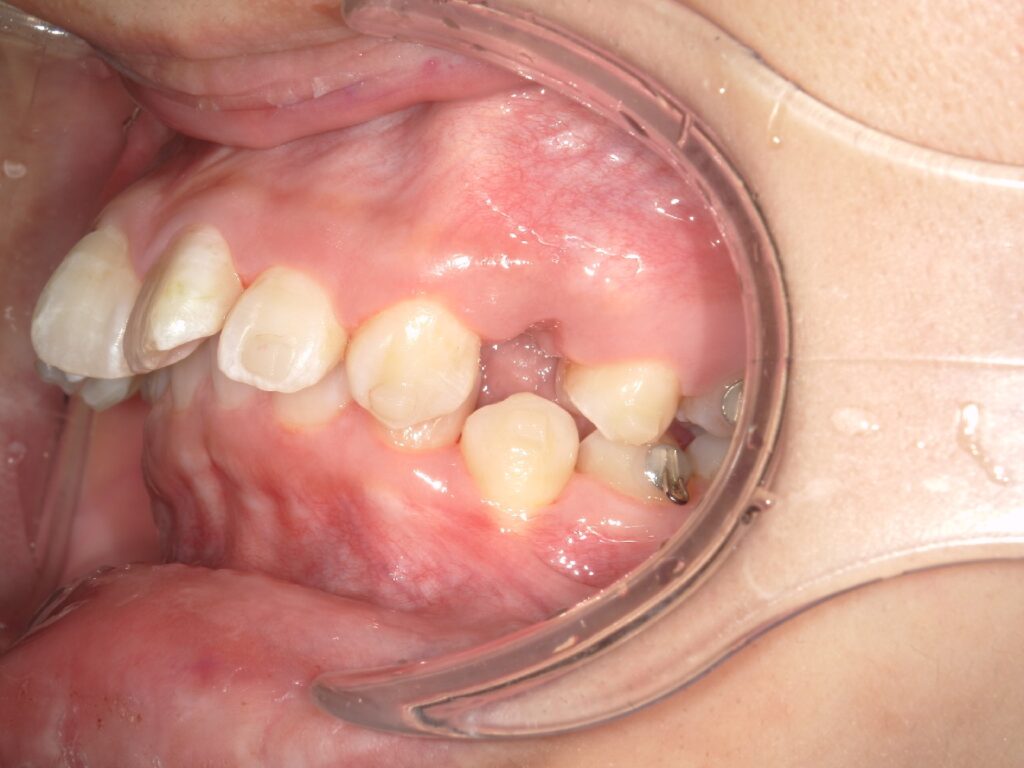

例えばこの患者様もマウスピース矯正中に歯茎が腫れてしまいましたが、適切に対応することで、現在では問題なく治療が進んでいます。当院では、そのようなトラブルがあってもラインにて対応ができるので、安心とおっしゃっていただく患者様が多いです。

食べ物がつまり、上記の部分が腫れて痛みがあり、マウスピースの装着が困難な状態でしたが、清掃指導及びマウスピースの辺縁を調整することで、治療の中断することなく、矯正治療を進めることができました。その後、患者様もフロスや歯間ブラシを使っていただくことで、良好に経過しています。